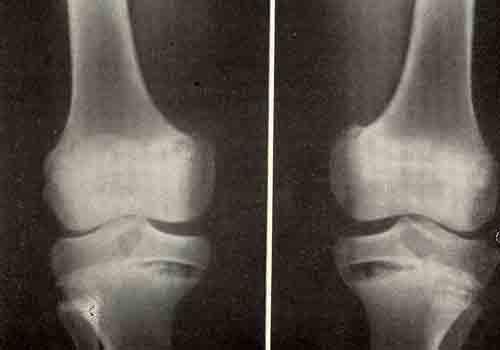

Рекурвация коленного сустава: рентгеновские снимки и восстановление